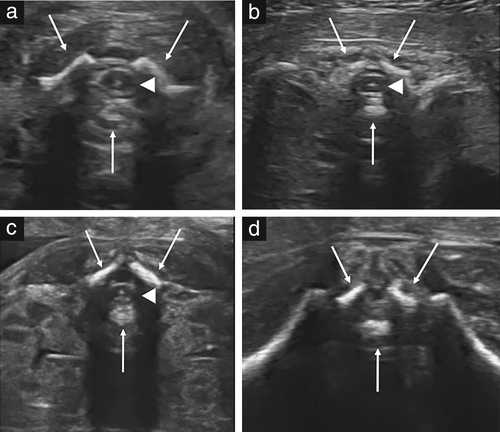

胎儿脊柱的详细检查需要专业知识和细致的扫描,其结果在很大程度上取决于胎儿的位置。因此,在每个平面上对胎儿的脊柱进行全面而详细的评估并不是筛查的一部分。最常见的严重脊柱异常之一是开放性脊柱裂,通常与颅内解剖结构异常有关:高达97%的病例出现所谓的“香蕉征”,这是由Chiari-II畸形引起的,但是,如果技术上可行,则应寻求胎儿脊柱的纵切面,因为它可能至少在某些情况下揭示出其他脊柱畸形,包括椎骨异常和骶骨发育不全,尽管即使对专家而言,后者的诊断也可能具有挑战性, 因为妊娠中期尾椎的生理性非骨化状态。在正常情况下,孕18-24周的脊柱矢状切面显示出围绕神经管的三个椎骨骨化中心(一个是椎体,另外是每一侧在椎板与椎弓根交界处)。根据超声波束的方向,它们显示为两条或三条平行线(图3)。在单个椎骨的横断面上,三个骨化核的显示最佳(图4)。另外,应该尝试以横切或纵切的来证明覆盖脊柱的皮肤的完整性。

三个骨化中心,箭头指示脊髓,在颈椎,胸椎和腰椎水平观察到。高回声点对应于髓质中央管。在水平(d),仅观察到马尾纤维

图4胎儿脊柱的不同位置的横断图:(a)颈椎,(b)胸椎,(c)腰和(d)骶椎。箭指示椎骨的三个骨化中心,箭头指示脊髓,在颈椎,胸椎和腰椎水平观察到。高回声点对应于髓质中央管。在水平(d),仅观察到马尾纤维。